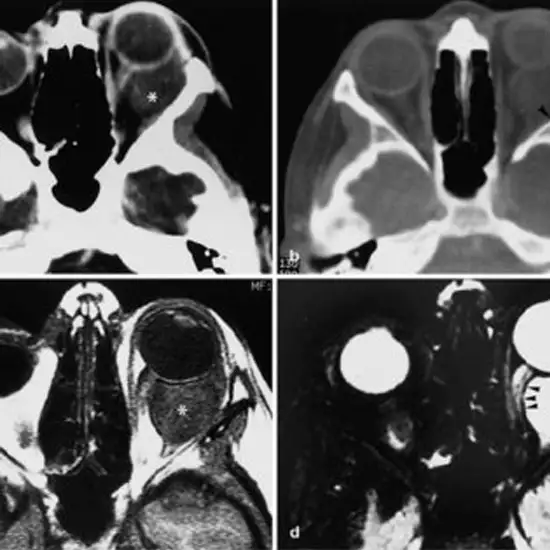

CECT Orbit Coronal is Contrast Enhanced Computed Tomography Orbit Coronal. This scan is used to evaluate the orbits, eyes, and surrounding soft and bony tissues. The orbit is the region of the eye socket. Contrast media is given to the patient to highlight the specific area.

CECT Orbit Coronal is Contrast Enhanced Computed Tomography Orbit Coronal. This scan evaluates the orbits, eyes, and surrounding soft tissues and bony/hard tissues.

A contrast-enhanced computed tomography scan of orbit is a diagnostic imaging method that uses X-rays or radiations to produce the detailed images of the eye sockets (orbits), eyes, and surrounding structures.